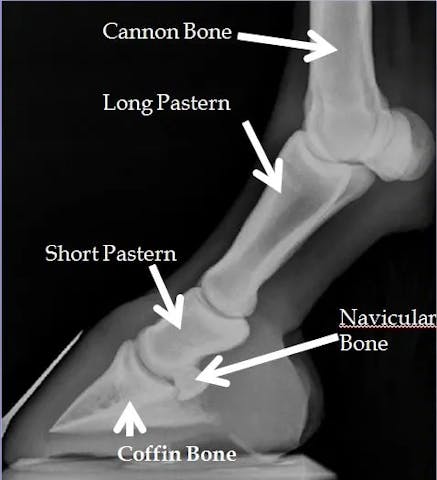

The short pastern bone is the middle phalanx in a horse's digit and is situated between the long pastern bone (the second phalanx, or P2) and the coffin bone (the third phalanx, or P3). It is a relatively short, sturdy bone located just above the hoof and below the fetlock joint.

The short pastern bone, along with the long pastern bone and coffin bone, plays a crucial role in supporting the horse's weight and facilitating movement. These three phalanges form the digital apparatus, and their coordination is essential for proper flexion and extension of the limb.